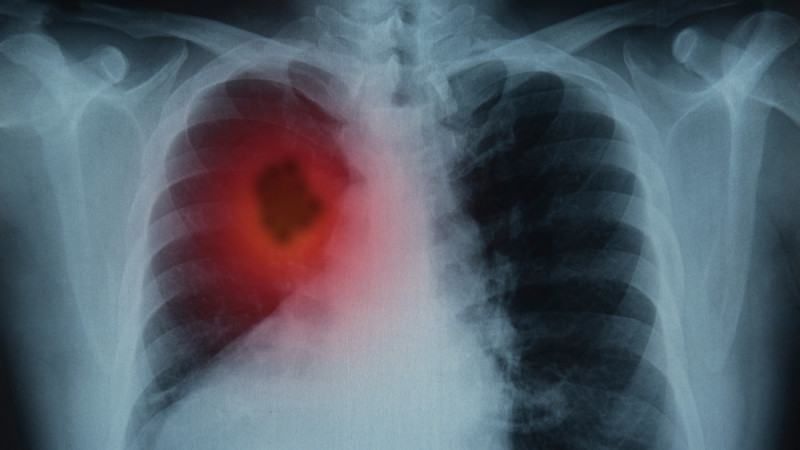

НДКТ-скрининг: эффективный метод диагностики агрессивного рака легкого

Рак легкого представляет собой одно из самых агрессивных онкологических заболеваний. Однако благодаря НДКТ-скринингу, который способен выявить заболевание на ранних стадиях, можно спасти миллионы жизней. Об этом в интервью рассказал профессор и заслуженный врач Петр Яблонский.

По словам профессора, медицинское сообщество активно поддерживает внедрение низкодозной компьютерной томографии (КТ) для скрининга. Если рак легкого обнаруживается на первой стадии, пятилетняя выживаемость пациентов составляет от 92 до 98 процентов.